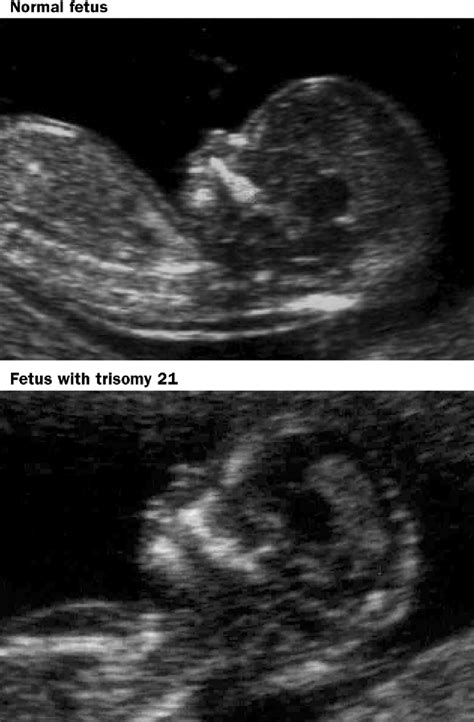

Down syndrome, also known as Trisomy 21, is a genetic condition caused by an extra copy of chromosome 21. While it cannot be diagnosed solely by looking at an image, certain physical features or markers can be identified during routine prenatal scans. When a sonographer or doctor talks about markers for Downs syndrome on ultrasound, they are referring to anatomical characteristics that are statistically more common in fetuses with this condition than in those without it.

It is crucial to emphasize that the presence of one or more of these markers does not mean the baby definitely has Down syndrome. Conversely, many babies born with Down syndrome show no identifiable markers on their ultrasounds. These scans serve as a way to calculate risk rather than provide a definitive yes or no answer.

• down syndrome ultrasound vs normal